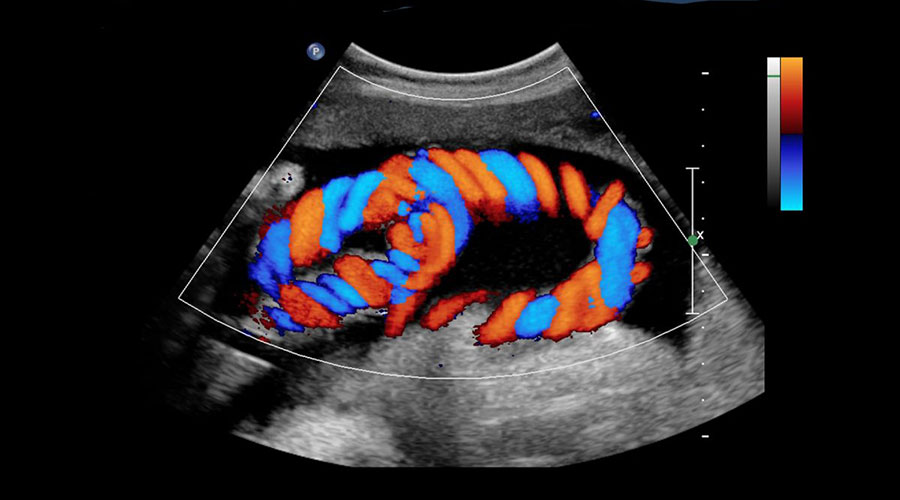

Цветной допплер, один из методов ультразвуковой визуализации, используется для обнаружения кровотока в сосудах и визуализации органов внутри тела с помощью высокочастотных звуковых волн. Сначала через зонд проходят звуковые волны. Аналогичным образом возвращающиеся звуковые волны собираются зондом и преобразуются в электрическую энергию. Он также преобразуется в изображение на компьютере. Он используется при обследовании многих частей тела. Основные области использования: Его можно кратко охарактеризовать как внутрибрюшные органы, поверхностные органы, такие как щитовидная железа, грудь, наблюдение за беременностью, сердце, артерии и вены.